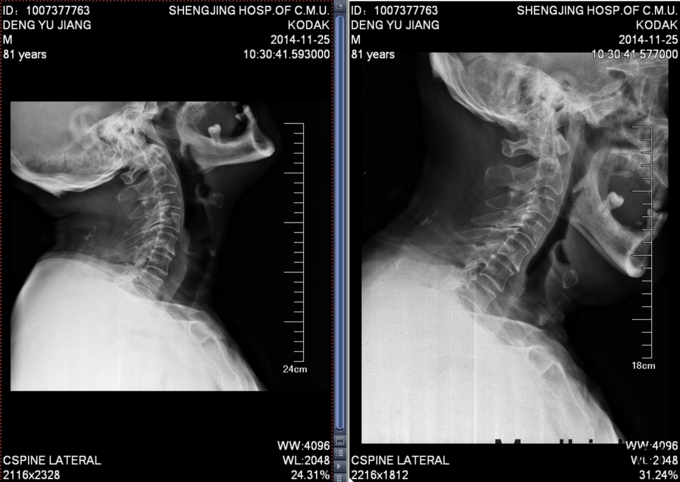

患者男,81岁,自述于1个月前出现双上肢感觉减退,发胀,以左侧为重,后来加重,左侧握力减退,于201医院就诊,行颈椎MR检查,提示为颈3-4、4-5间盘突出,为求进一步治疗就诊于我院,患者病来饮食、睡眠佳。大小便正常,体重无明显变化。

颈椎生理弯曲消失,活动度正常。双上肢感觉减退。双手握力(R5级,L4级),伸肘肌力(R5级,L5级),屈肘肌力(R5级,L5级),Hoffman(R-,L+)桡动脉搏动有力,末梢血运良。

诊断:颈椎病,颈椎间突出,高血压病 患者入院后完善相关检查,请相关科室及麻醉科会诊,医院医务部审批后,查无其他手术禁忌症,于全麻下行颈椎后路单开门椎管扩大减压侧块螺钉内固定术。术后给予患肢雾化祛痰,抗炎,消肿,营养神经,接骨等对症治疗。术后患者在颈领的保护下可下地行走,术后14天拆线后予以出院,